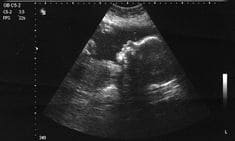

난임 치료는 크게 인공수정, 체외수정(IVF), 난자채취와 같은 방법이 일반적입니다.

이외에도 남성난임 치료를 위한 정자 운동성 향상 치료, 정자 추출 수술 등이 있으며, 최근에는 한방 난임 치료도 많은 관심을 받고 있습니다.